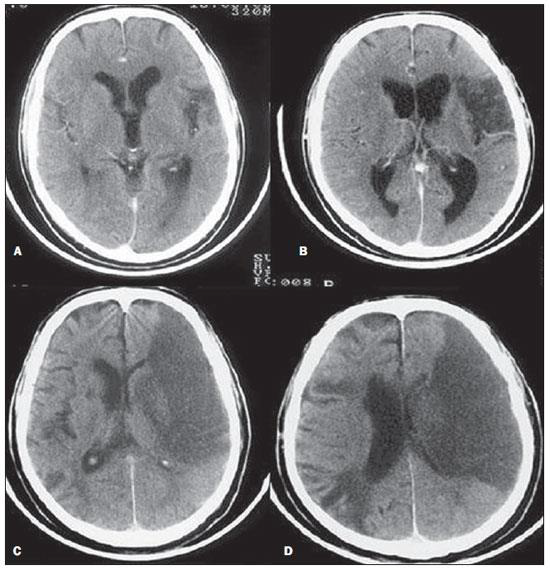

Analise a tomografia abaixo e assinale a alternativa que indique, corretamente, o achado radiográfico:

Enunciado 2968770-1

http://www.rb.org.br/detalhe_artigo.asp?id=2613&idioma=Portugues

Observe a imagem tomográfica abaixo, analise os excertos e assinale a alternativa correta:

Enunciado 2968768-1

I – Tomografia Computadorizada com AVCI do território da Artéria Cerebral Posterior (ACP).

II – A;B - Infarto parcial, com envolvimento restrito ao hemisfério esquerdo.

III – C;D: Infarto completo à esquerda, com efeito de massa comprimindo o ventrículo lateral.

IV - No hemisfério direito visualiza-se hipodensidade esquerda maior.

Está correto o que se afirma em: